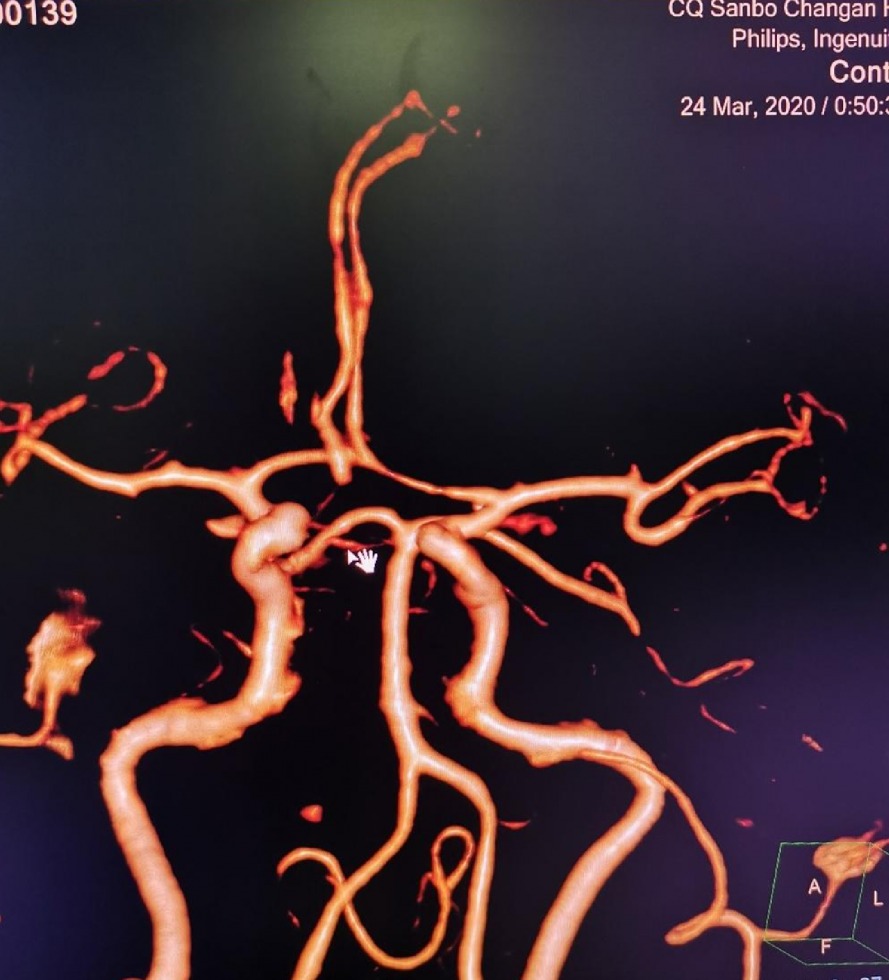

CTA 结果

术后CTA显⽰

术后CTA显⽰:畸形⾎管团消失